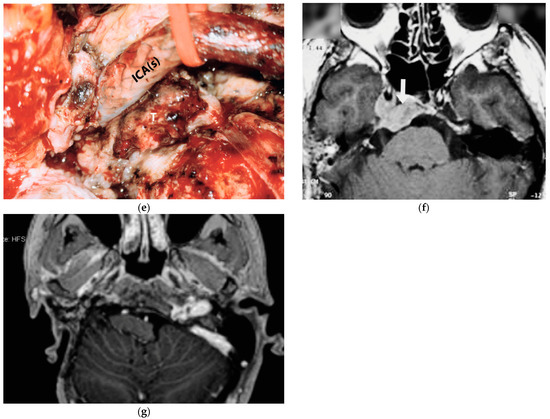

5.1. Case 1: (C4Di2)

5.2. Case 2: (C3Di1 + Stage I VP)

5.3. Case 3: (C4Di2Vi)

5.4. Case 4: (C3Di2 + Stage II Vagal PGL)

5.5. Case 5: (C3Di2Vi)

5.6. Case 6: (C4Di2Vi)